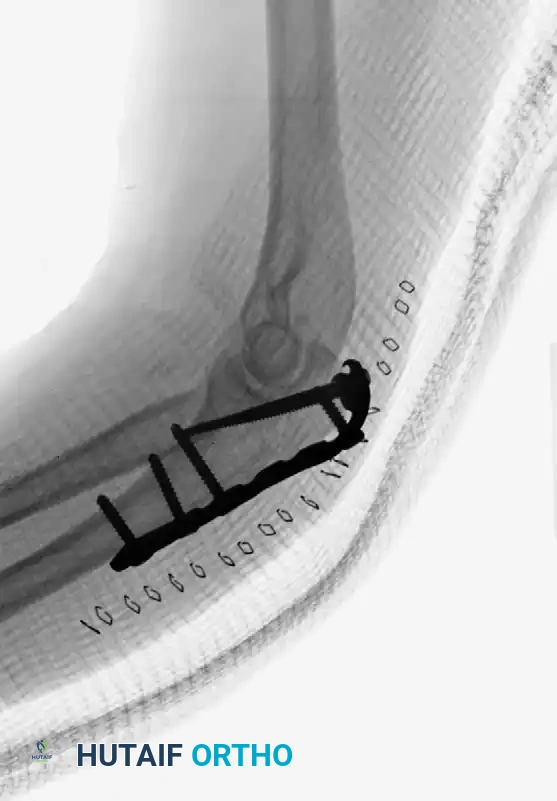

Complex Olecranon Fracture-Dislocation (Injury):

Fixation with Low-Profile Plate (AP View):

Fixation with Low-Profile Plate (Lateral View):

Plate-and-Screw Fixation: The Modern Gold Standard

Plate fixation is the contemporary treatment of choice, offering superior biomechanical stability. It is specifically indicated for fractures with comminution, distal extensions (Monteggia variants), and complex fracture-dislocations.

Typically applied in a neutralization mode, the plating technique allows for independent lag screw fixation of the olecranon and/or coronoid fragments to anatomically reconstruct the proximal ulna. The plate then spans the construct, providing the rigid stability necessary to initiate an early range-of-motion program.

While early literature cited symptomatic hardware as a disadvantage of plating, modern implant designs have largely mitigated this issue. Newer precontoured plates are anatomically designed, lower in profile, and feature locking screw capabilities. They can also be contoured to match the proximal ulnar bow for extended fractures. Biomechanical testing confirms that these modern plates provide significantly greater compression than tension bands, yielding favorable results in over 80% of patients.